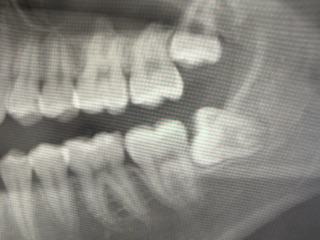

親知らず(第三大臼歯)は

10代後半〜生えることのある歯(骨の中に完全に埋まっていて生えてこない場合や、先天的に親知らずがない場合もあります。)

一番奥の歯で、横向きや埋没した生え方で痛み、腫れ(智歯周囲炎)、隣の歯の虫歯を引き起こしやすいです。しかし、必ず抜く必要はありません。まっすぐ生えて、また上下で噛み合わさっている、完全に埋まっているなどと、特に悪さをしていなければの話です。

1番奥の歯は歯ブラシが届きづらく、奥の奥まで磨くのは大変難しいのです。

半分又はちょっとだけ出ている場合は、虫歯になる前に抜いてしまう事をオススメいたします。痛みが出てる場合は、まず痛みが治まるのを待ってからの抜歯になります。そうすると抜歯まで時間がかかる場合があります。そして何より、若い内に抜歯すると、傷の治りが早い、痛みや腫れが少ない傾向にあります。

横向きや半分だけ埋没している親知らずの抜歯は、当院では出来かねますので、まずはご相談ください。